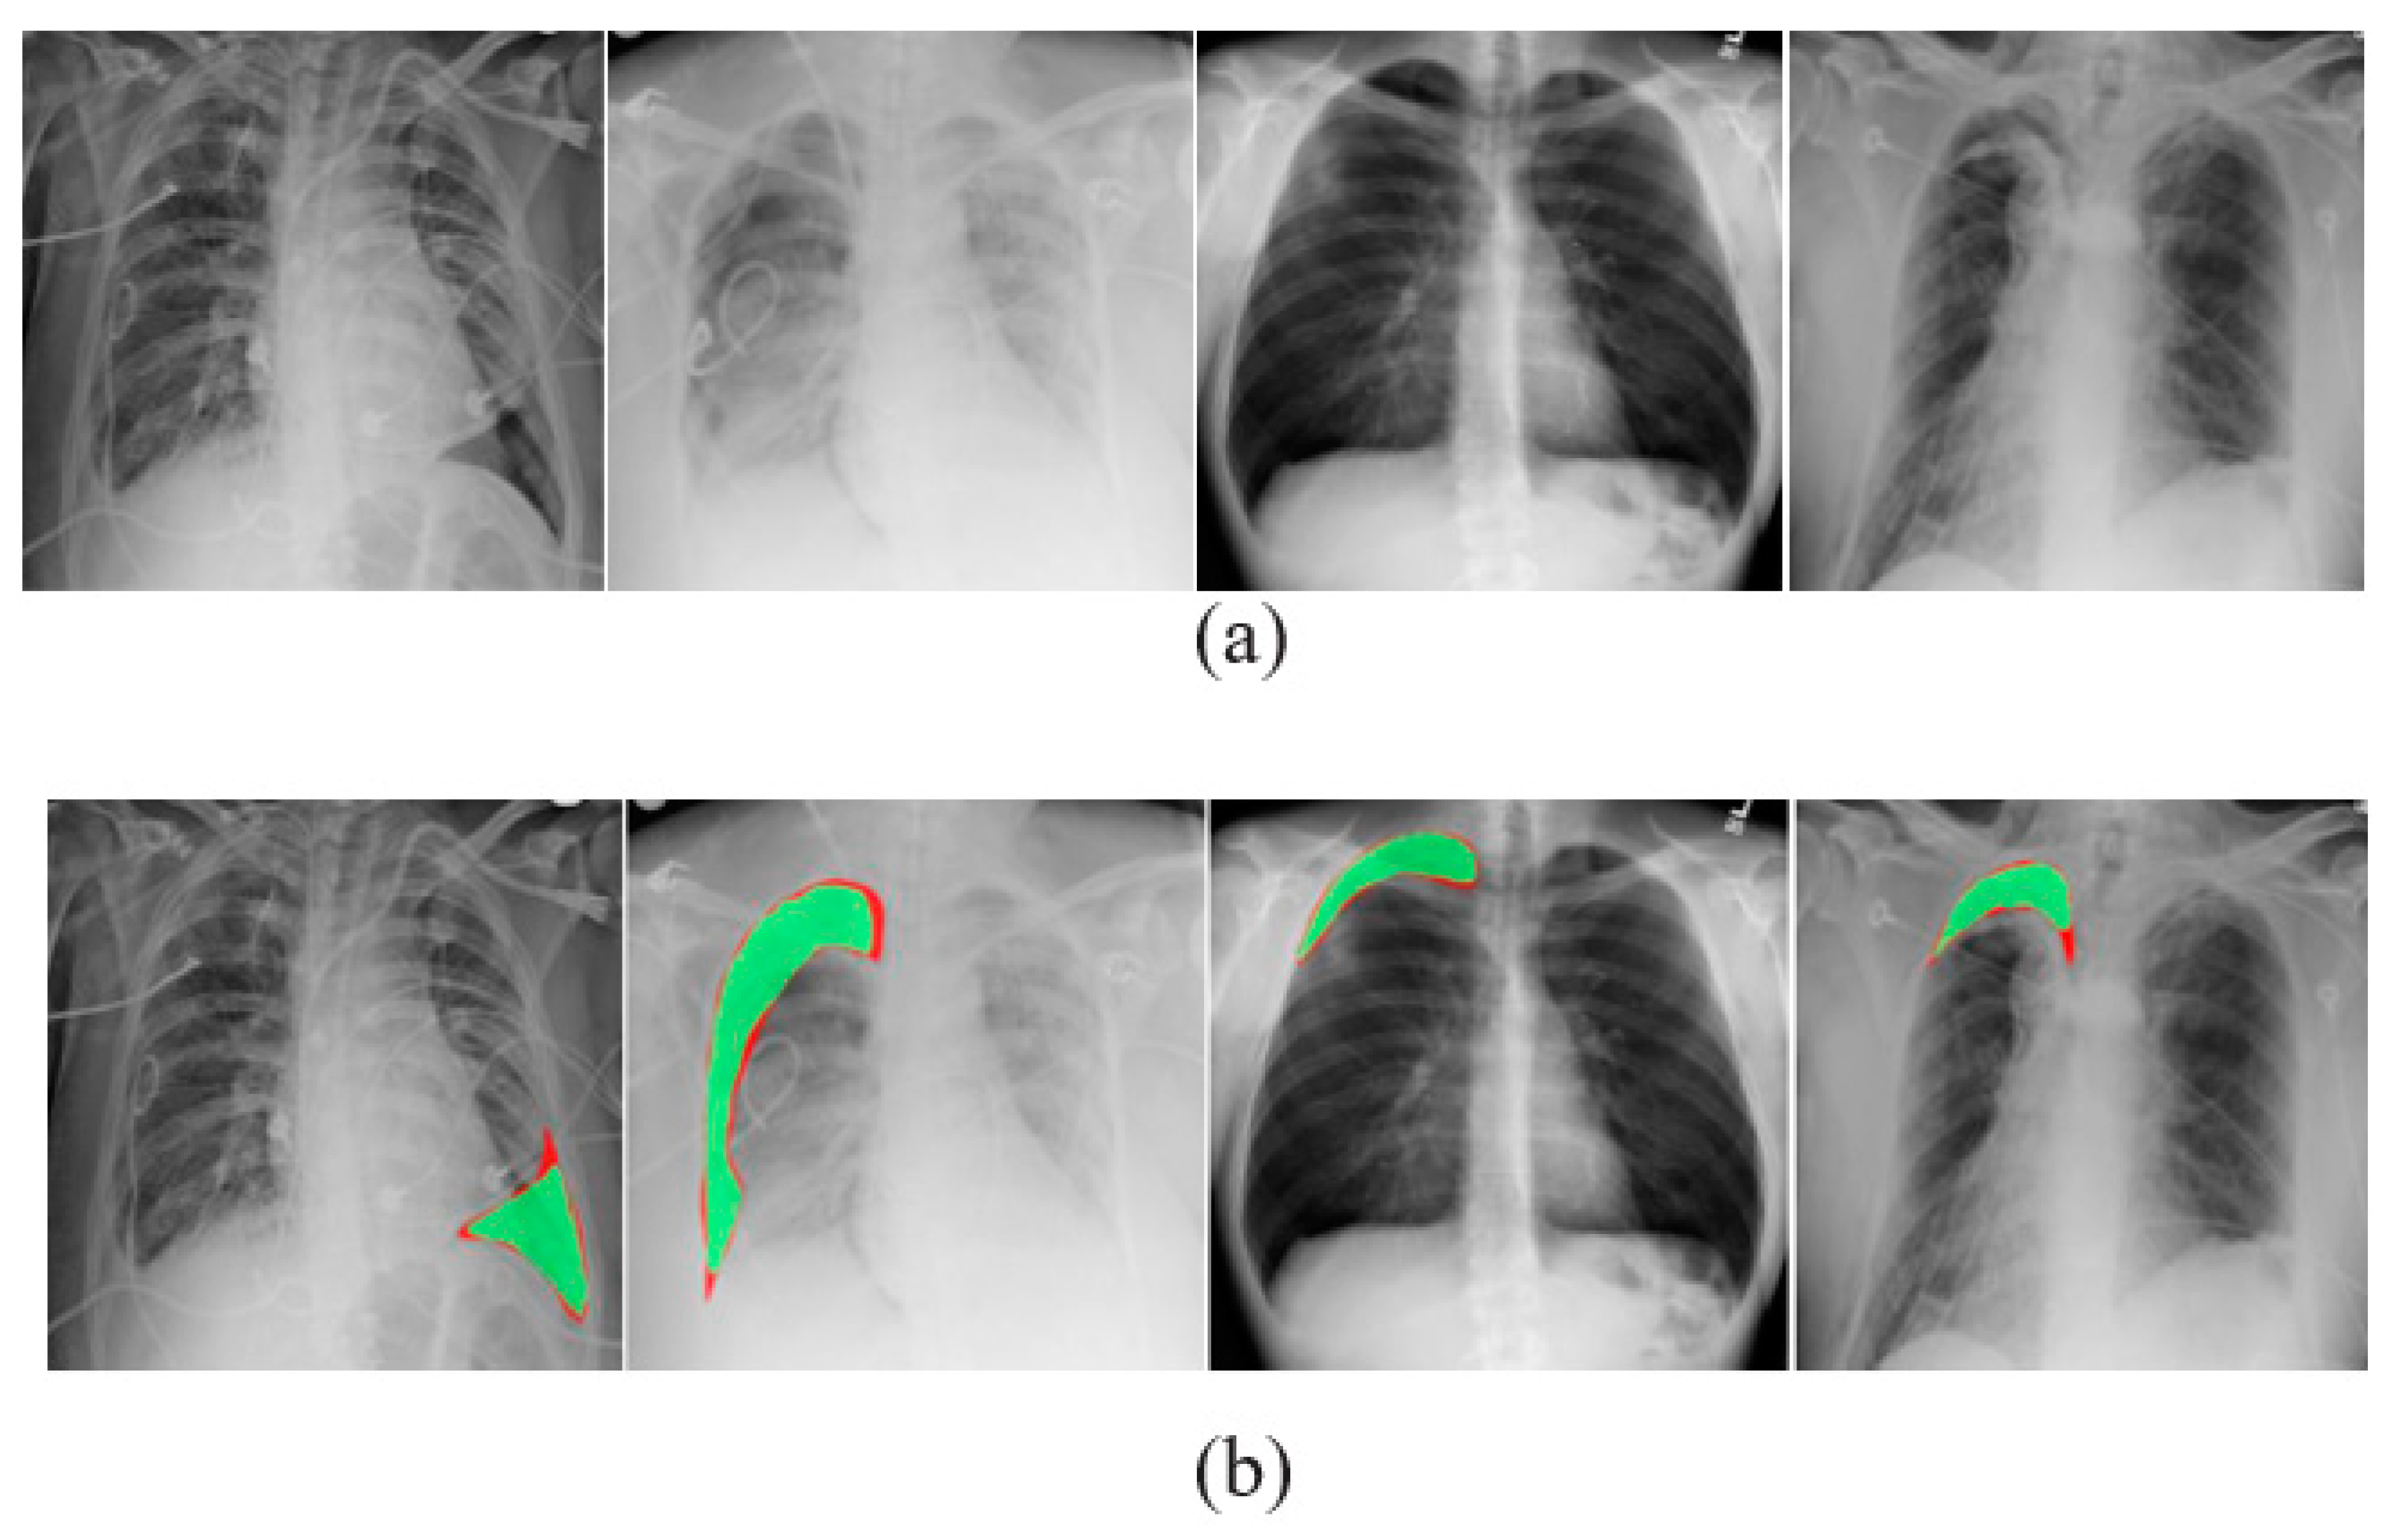

3.3. Data Augmentation

3.4. Image Segmentation